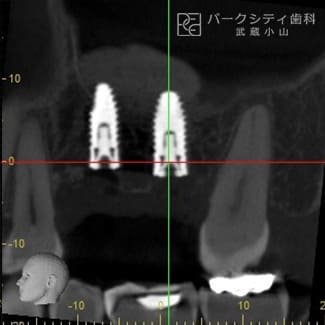

GBRに上顎洞挙上術を併用し、インプラント治療した症例

- GBR法(骨誘導再生法)

上顎洞挙上術

インプラント埋入

顎骨が足りなく他医院でインプラント治療を断られた方のケースです。大規模なGBRと上顎洞挙上術を用いて顎骨を確保し、インプラント治療をおこないました。